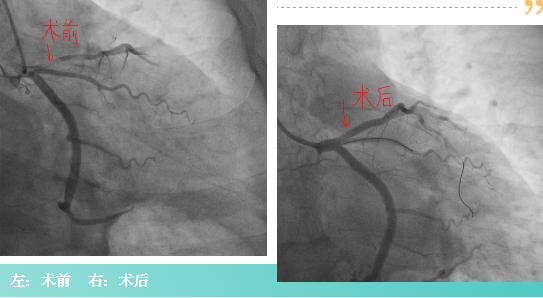

冠脉造影术中发现患者前降支血管狭窄99%,且冠脉内形成大量新发血栓。术中应用冠脉内尿激酶溶栓术、球囊扩张成形术及冠脉支架置入术,顺利为患者开通了闭塞的前降支血管,挽救了濒临坏死的心肌,避免进一步出现严重心力衰竭风险,成功挽救了患者的生命。